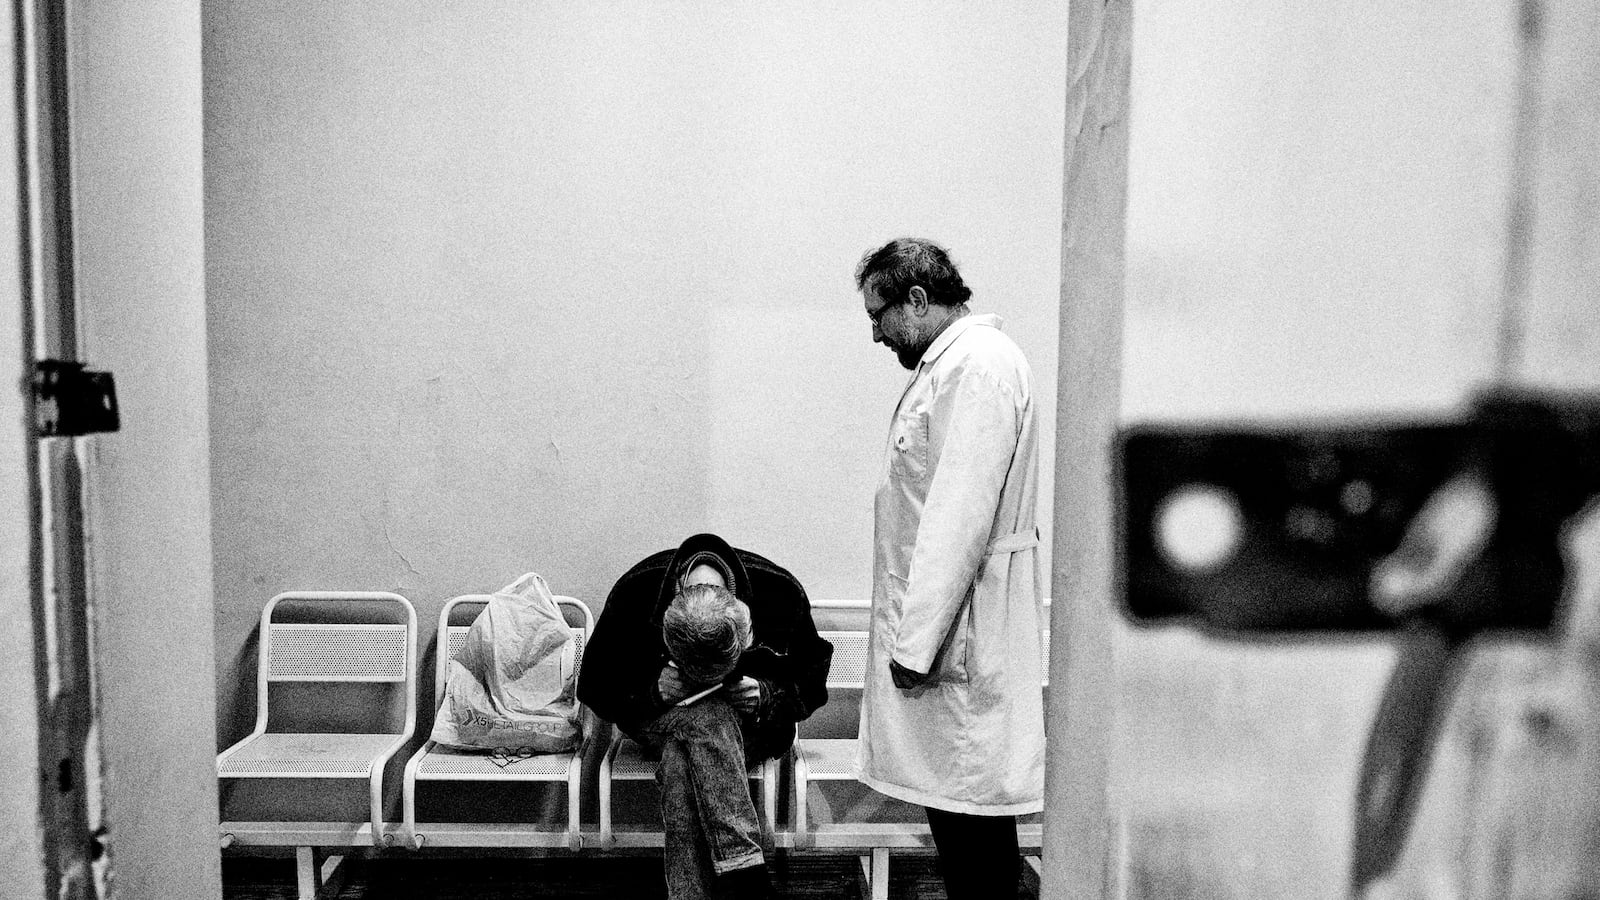

A TB patient and intravenous drug user begs his doctor for pain medication.

Anatoly, 45, a doctor at the Botkin Infectious diseases hospital, is in charge of the clinic in town treating homeless people. He sees many people coming in with tuberculosis symptoms and tries to get them admitted into hospitals for treatment.

Anatoly, 45, doctor at the Botkin Infectious diseases hospital, is in charge of the clinic in town treating homeless people. He sees many people coming in with tuberculosis symptoms and tries to get them admitted into hospitals for treatment.